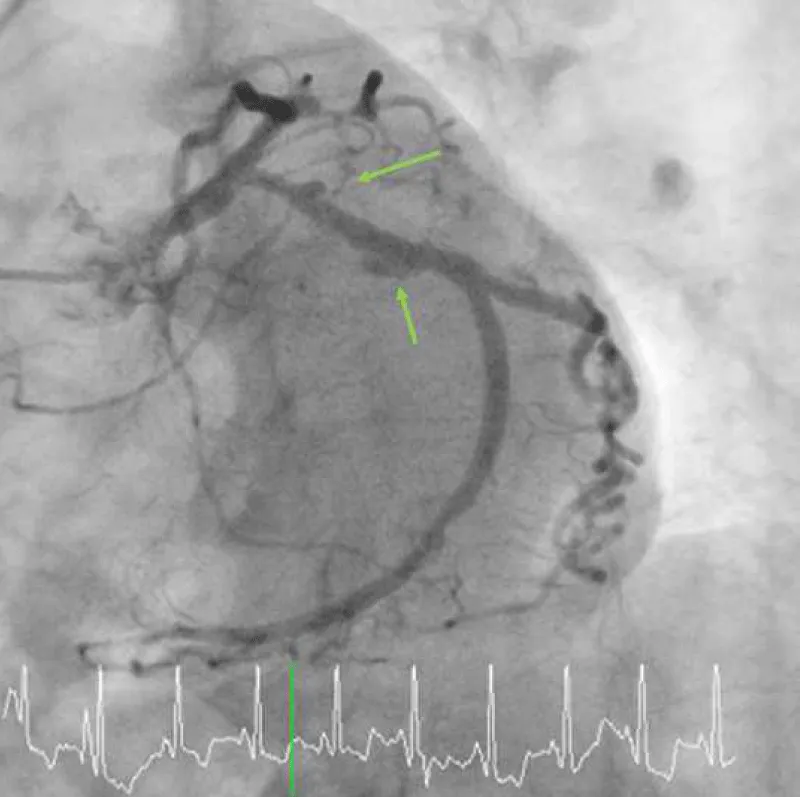

A 75-year-old woman presented with new-onset Canadian Cardiovascular Society Classification Class III angina. A coronary angiogram revealed a 90% blockage of the distal left main trunk (LMT) and a 99% blockage of the ostial left anterior descending coronary artery (LAD) (Video 1A) and (Video 1B). The Syntax Score, Society of Thoracic Surgeons (STS) score and left ventricular ejection fraction (LVEF) were 28, 1.65% and 74%, respectively. A 3.0 × 18-mm CYPHER™ stent had previously been implanted into the dominant proximal circumflex artery (LCx) in 2009 because of unstable angina (Figures 1A,1B). Although some persistent peri-stent contrast staining (PSS) was noted on an angiogram as early as June 8, 2015 (Figure 1C), a single treatment with clopidogrel for antiplatelet therapy was interrupted 7 days before an elective CABG. The patient started complaining of chest pain that corresponded with a marked ST elevation in the inferior posterior leads (Figure 2) and subsequently collapsed on August 7, 2016, in a general ward, 5 days after clopidogrel was discontinued. The patient had a history of dyslipidemia and hypertension but not diabetes, prior cerebrovascular accident, or chronic obstructive pulmonary disease. Her medication included clopidogrel (75 mg), rosuvastatin (2.5 mg), nicorandil (15 mg) and benidipine (8 mg) daily. An emergent bedside echocardiogram showed posteroinferior hypokinesia without any dissection flap in the aortic root (Video 2). Following an aggressive cardiopulmonary resuscitation (CPR) in the general ward, femorofemoral venoarterial extracorporeal membrane oxygenation (VA-ECMO) was inserted in a catheterization laboratory (Video 3). An emergent angiogram revealed a thrombotic stent occlusion of the proximal LCx (Video 4A) and (Video 4B). During angiography, the patient remained pulseless and suffered repeated bouts of ventricular fibrillation, which necessitated defibrillations. When manual aspiration thrombectomy was performed, adequate coronary flow returned instantaneously (Video 5) and (Video 6) and systolic blood pressure improved to 90 mmHg. In the end, an intra-aortic balloon pump was placed and ECMO could be tapered off the same day. The maximum creatine phosphokinase and creatine kinase-MB levels were 4398 and 269 IU/mL, respectively. The following day, the patient underwent on-pump CABG with left internal thoracic artery-LAD and saphenous vein graft-obtuse marginal anastomoses. The patient survived and recovered well without any neurological defect. As of today, LVEF is 55% and single clopidogrel therapy is ongoing. Both bypass grafts and the stent were patent (Video 7).

Figure 1A: A diagnostic angiogram and PCI in 2009 and a follow-up angiogram in 2015. A baseline angiogram using a 4-Fr Judkins diagnostic catheter via transradial access shows a focal 90% blockage (yellow arrow) at the dominant proximal LCx.

Figure 1C: Multifocal peri-stent contrast staining is depicted by green arrows, which was observed in 2015. LCx: Left Circumflex; PCI: Percutaneous Coronary Intervention.